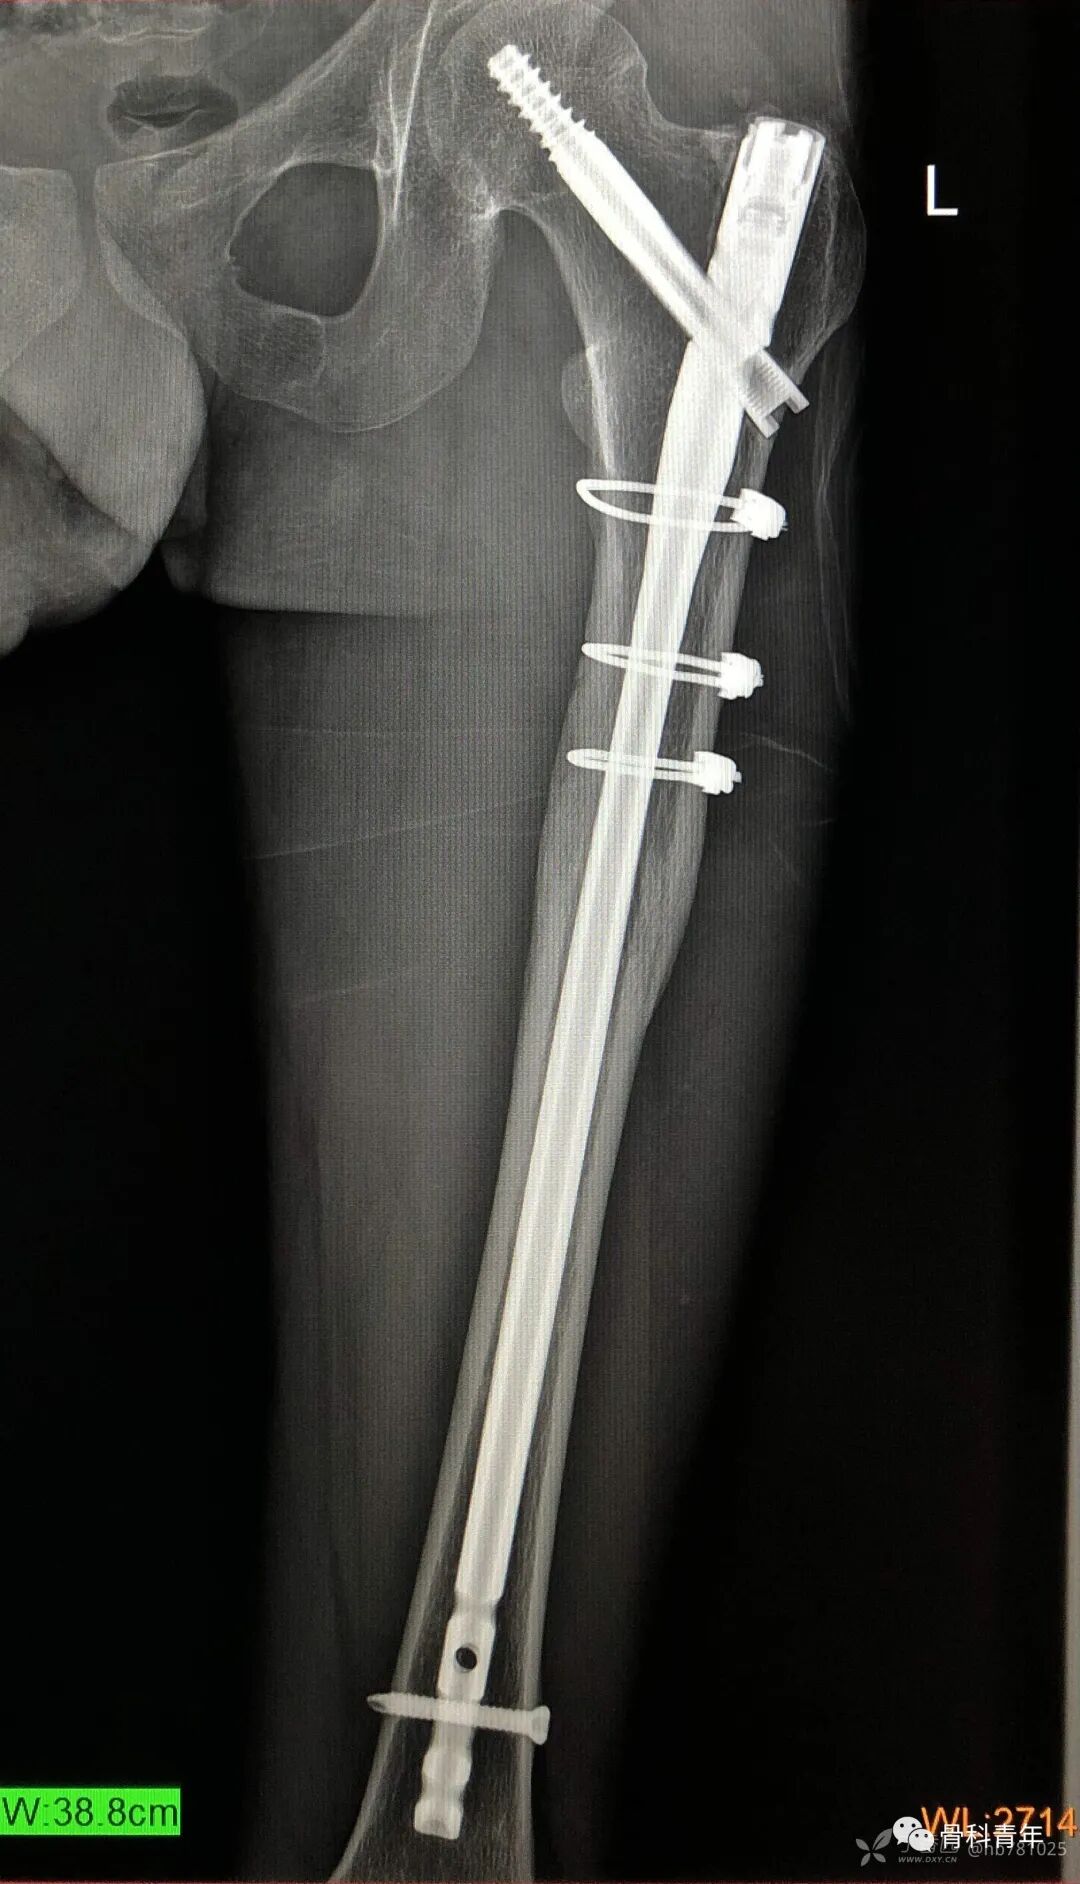

4.股骨骨折(髓内钉)